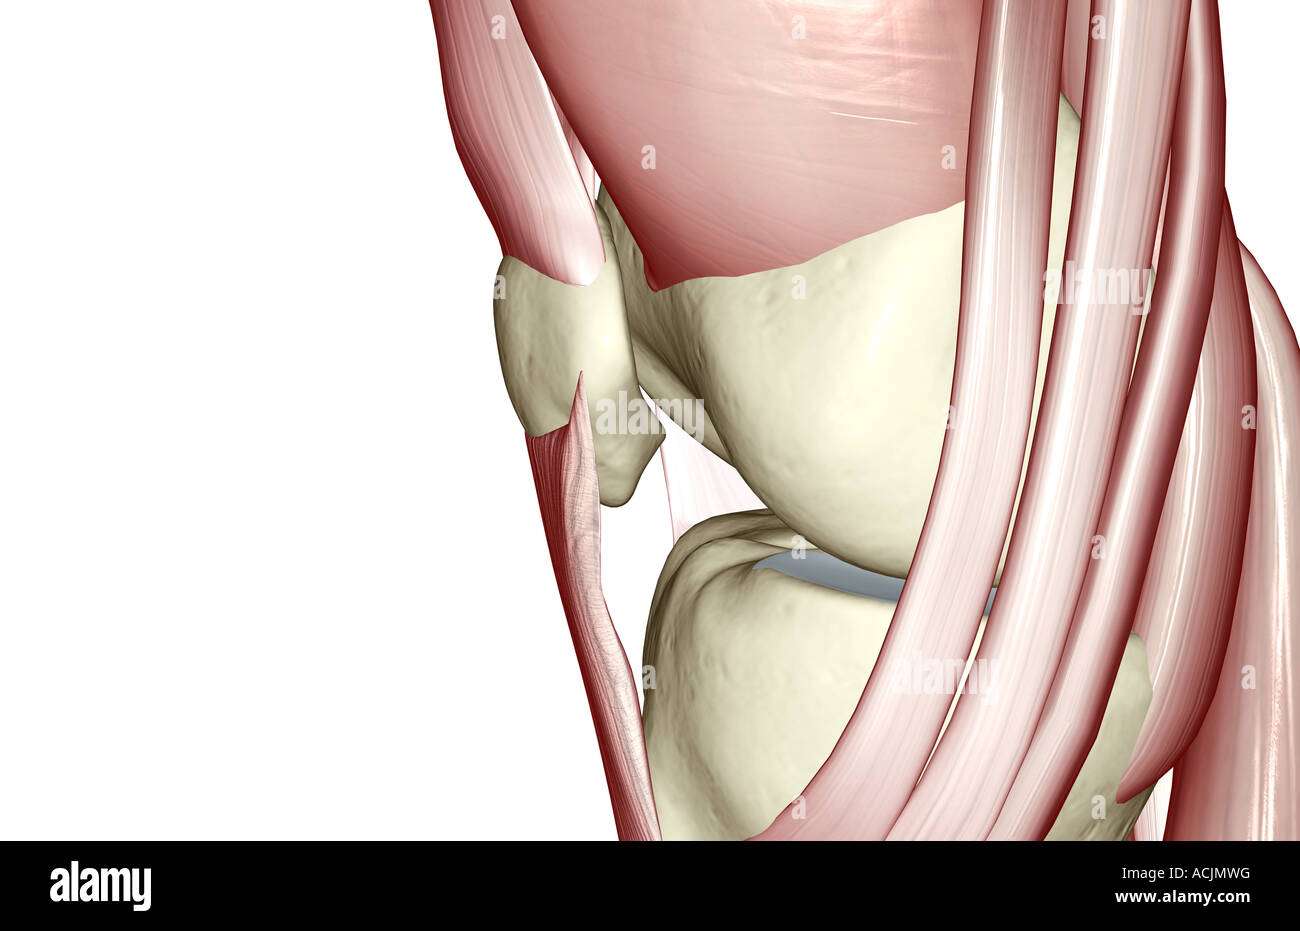

Schmerzen im Knie Ursachen & Therapie Knorpelexperte.de. **Alles über Sehnen im Knie: Funktion, Verletzungen und Behandlungsoptionen** Das Knie ist eines der komplexesten Gelenke im menschlichen Körper und enthält zahlreiche Sehnen, die eine wichtige Rolle bei der Stabilisierung und Bewegung des Gelenks spielen. Wenn die Sehne jedoch schon erheblich vorgeschädigt ist, so dass ein dauerhafter Schmerz besteht, verringert dieser sich möglicherweise durch den Sehnenriss.